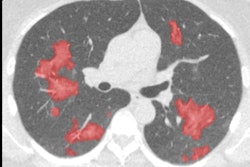

The application of energy normalization improved CAD's ability to distinguish normal (top row) from abnormal (bottom row) chest radiographs.

The application of energy normalization improved CAD's ability to distinguish normal (top row) from abnormal (bottom row) chest radiographs.Energy normalization works well, improving the robustness of the CAD system for tuberculosis, Philipsen concluded. The process "can be used reliably on data from different x-ray units and has great potential in TB screening," he said.